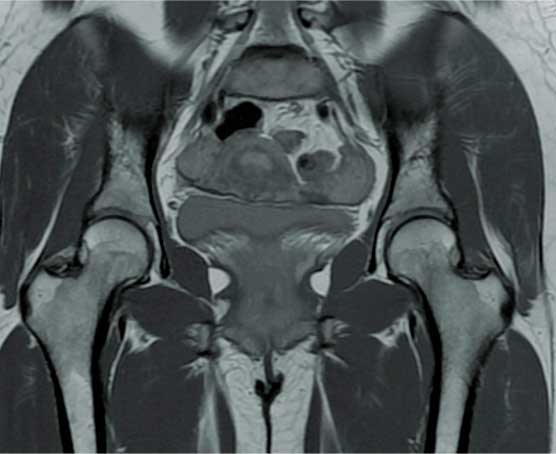

Prótesis de cadera

Es también conocida como reemplazo de cadera, la cual consiste en la sustitución de la articulación dañada o un implante de metal, cerámica o plástico que realiza la función de la articulación, mejorando el dolor.

Las indicaciones más comunes son la artrosis o desgaste de cadera en adultos mayores, otras indicaciones son las fracturas de cadera, el daño crónico o infección, artritis reumatoide, secuelas de enfermedades de la cadera o traumatismos, las cuales se presentan en adultos jóvenes y adultos mayores.

El paciente puede caminar desde el mismo día de la cirugía, se da de alta a su domicilio a las 24 horas y puede realizar actividades cotidianas en casa de forma autónoma desde la primera semana. La recuperación parte en un 80% de la función de la cadera en el primer mes, 90% de la función en el segundo mes y 92% - 98% de la función en el tercer mes.

Eliminar el dolor en la zona afectada, mejorar la función como es fuerza muscular, movimiento, estbilidad y biomecánica, logrando mejorar la calidad de vida del paciente.